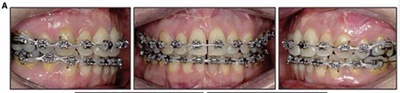

擴(kuò)弓保持8周后,除擴(kuò)弓器影響牙外粘接托槽,使用0.014鎳鈦絲進(jìn)行排齊、整平。旋轉(zhuǎn)停止后3個(gè)月拆除擴(kuò)弓器,全口粘接托槽,使用0.016niti繼續(xù)排齊整平。佩戴可摘保持器,保持上頜寬度。在使用至0.018x0.018niti7周,徹底排齊整平后,使用大弓型的0.016x0.022不銹鋼絲,繼續(xù)維持原有寬度,同時(shí)停止使用可摘保持器。掛II類(lèi)牽,糾正磨牙關(guān)系,使用鏈圈關(guān)閉散在間隙,少量使用IPR去除局部前牙的黑三角。術(shù)后9個(gè)月拍全景示,牙根平行度可,再無(wú)其他牙根出現(xiàn)問(wèn)題。1年7個(gè)月后治療結(jié)束。上下頜3-3舌側(cè)保持器+哈雷氏保持器進(jìn)行保持。

患者側(cè)貌改善,下唇唇肌緊張消失,上下唇可自然閉合。磨牙及尖牙關(guān)系糾正至I類(lèi),覆合覆蓋正常。上下頜弓型糾正至卵圓形,牙弓寬度增加。頭影測(cè)量分析示SNA角81.8°,ANB角3°。頭影測(cè)量重疊圖示下頜骨向后旋轉(zhuǎn),垂直面高度略有增加。